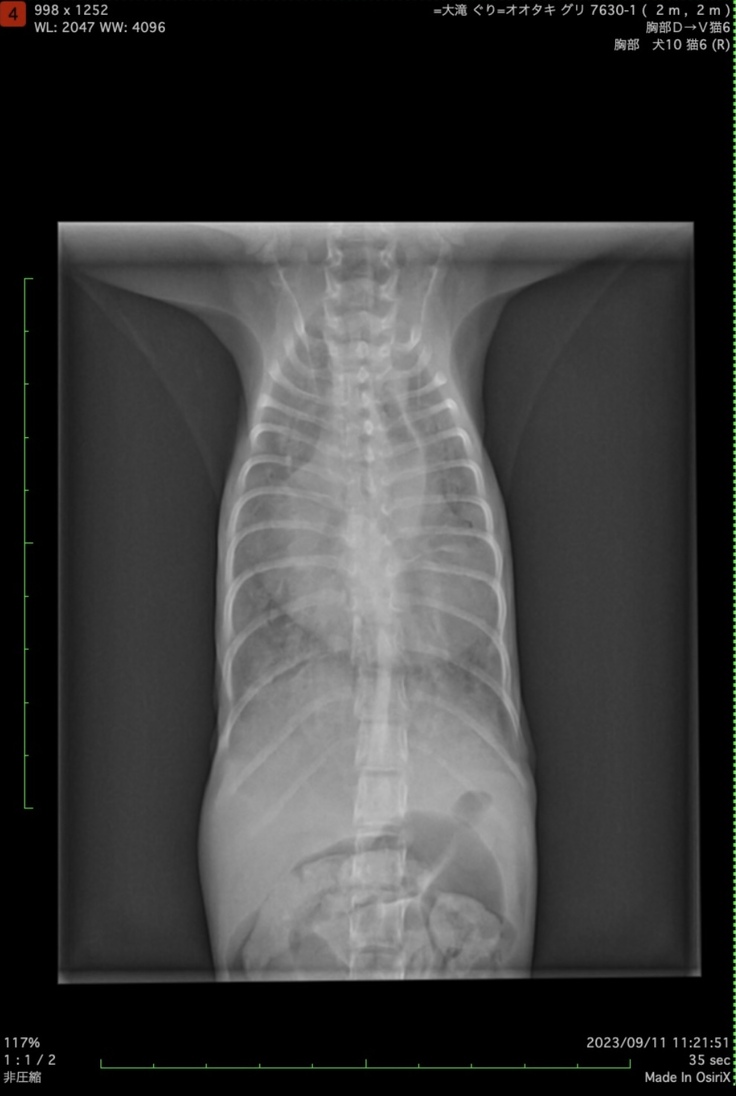

9/11

そのときのレントゲン写真です。

心臓がパンパンで肺が真っ白…